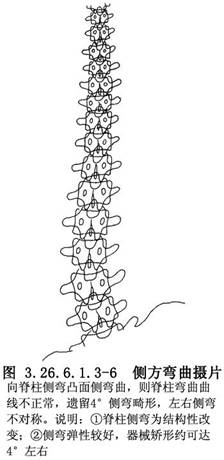

(2)攝臥位雙側彎曲脊柱正位相或懸吊位相。其意義是:瞭解脊柱側彎是結構性或是非結構性;了解結構性側彎(原發性側彎)的範圍,以確定脊柱融合的椎體範圍;瞭解畸形脊柱的彈性,估計術中器械矯形可達角度。向側彎凸側彎曲時結構性側彎的角度改變,大約與術中器械矯形可達到的角度一致(圖3.26.6.1.3-4~3.26.6.1.3-6)。